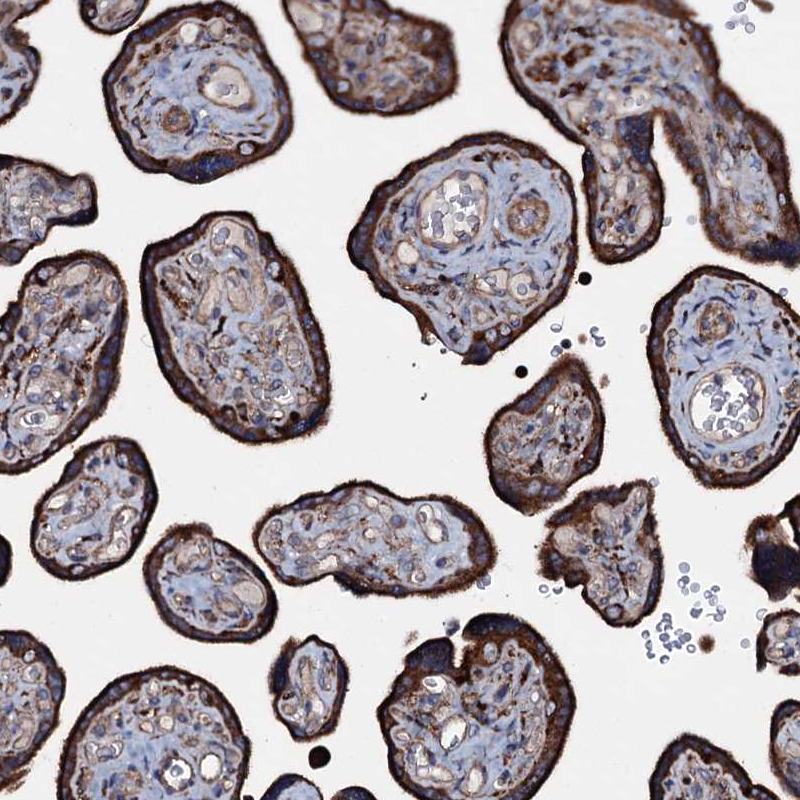

Immunohistochemistry analysis in human placenta and skeletal muscle tissues using HPA039494 antibody. Corresponding P2RX4 RNA-seq data are presented for the same tissues.